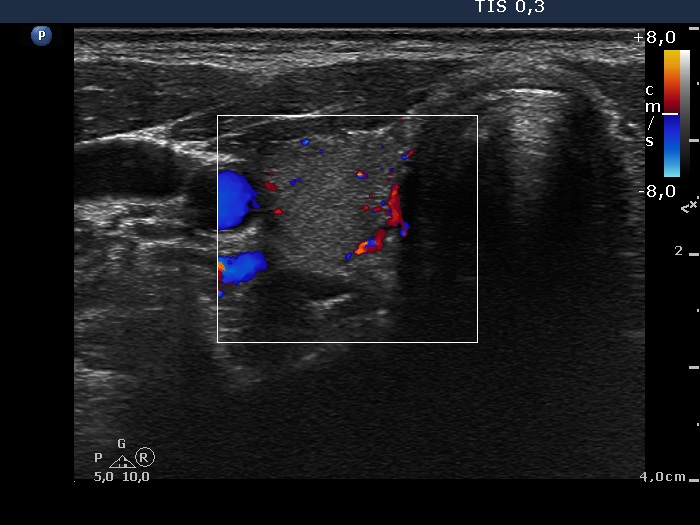

Follow-up examination 3 months later (2nd row of images):

Clinical presentation: The complaints of the patient ceased.

Palpation: The thyroid was not tender, both lobes were firm.

Functional state: hypothyroidism with TSH 2.98 mIU/L and FT4 7.56 pM/L. CRP 1.9 mg/L.

Ultrasonography: The proportion of hypoechogenic areas has decreased. The vascularization became normal.